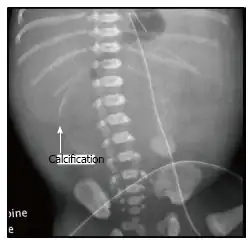

| X-ray of a newborn with meconium pseudocyst resulting from bowel perforation. In this case the cause was atresia of the terminal ileum. There is a fine rim of calcification surrounding the big pseudocyst which shifts the other intestinal structures outwards. | |

Meconium peritonitis is sometimes diagnosed on prenatal ultrasound[3] where it appears as calcifications[4] within the peritoneum.